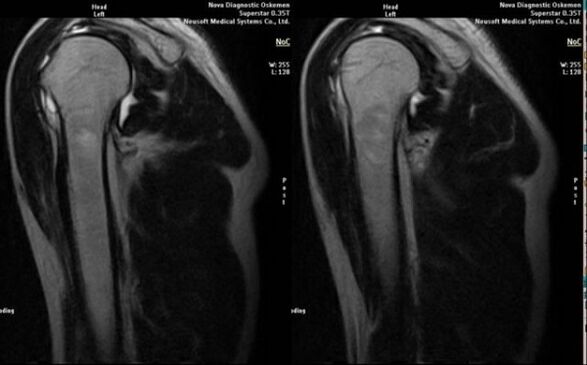

- magnetresonants ja kompuutertomograafia;

Artroosi arengule viitavad märgid hõlmavad liigeseõõne märkimisväärset ahenemist, kõhrealuste struktuuride skleroosi, kondrotsüütide kihi enda hõrenemist, osteofüütide ilmumist ja soolakristallide sadestumist intraartikulaarsesse vedelikku.